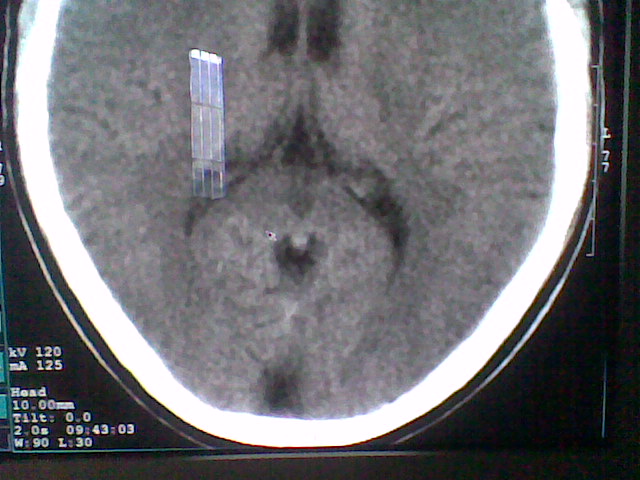

标题: CT21502:这个正常的么?

患者,男,头晕4天来诊,要求ct。

大枕大池合并蛛网膜囊肿。

支持 大枕大池合并蛛网膜囊肿。

考虑大枕大池合并蛛网膜囊肿。

有没有dandy-walker综合征的可能?